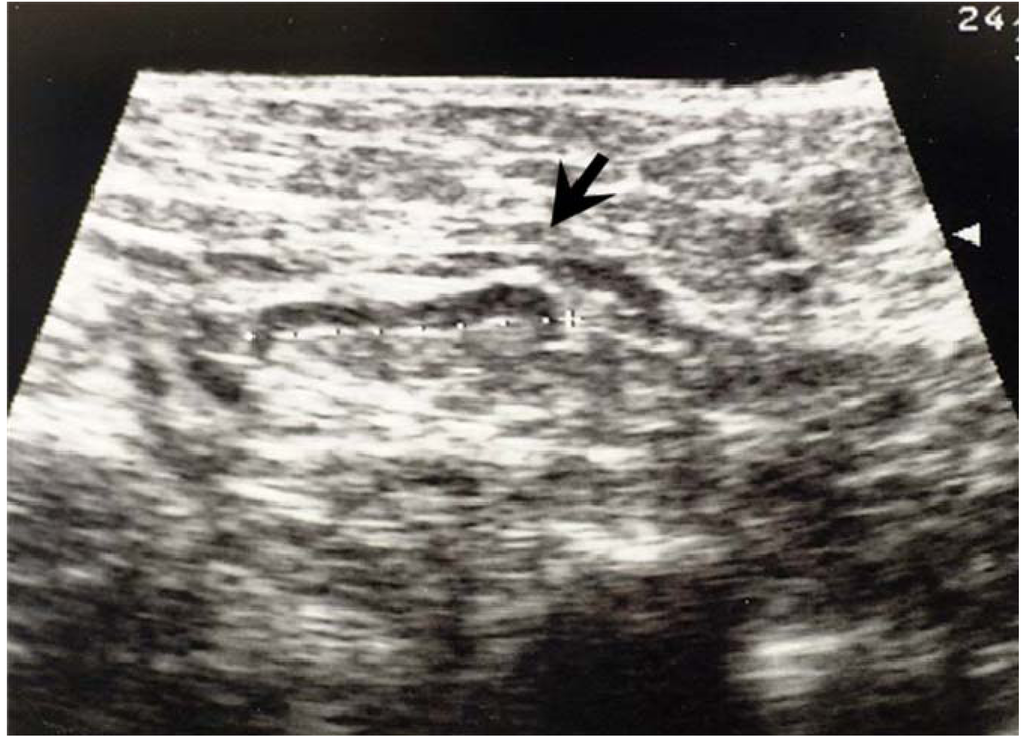

3.2. Ultrasonographic Examination and Criteria for Axillary node Evaluation